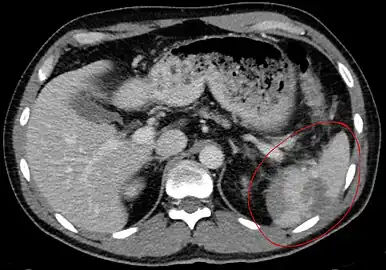

Traumatic rupture of the spleen on contrast enhanced axial CT (portal venous phase)

Splenic hematoma resulting in free abdominal blood

Splenic rupture is usually evaluated by FAST ultrasound of the abdomen.[3] Generally this is not specific to splenic injury; however, it is useful to determine the presence of free floating blood in the peritoneum.[3] A diagnostic peritoneal lavage, while not ideal, may be used to evaluate the presence of internal bleeding a person who is hemodynamically unstable.[4] The FAST exam typically serves to evaluate the need to perform a CT scan.[4] Computed tomography with IV contrast is the preferred imaging study as it can provide high quality images of the full peritoneal cavity.[3]